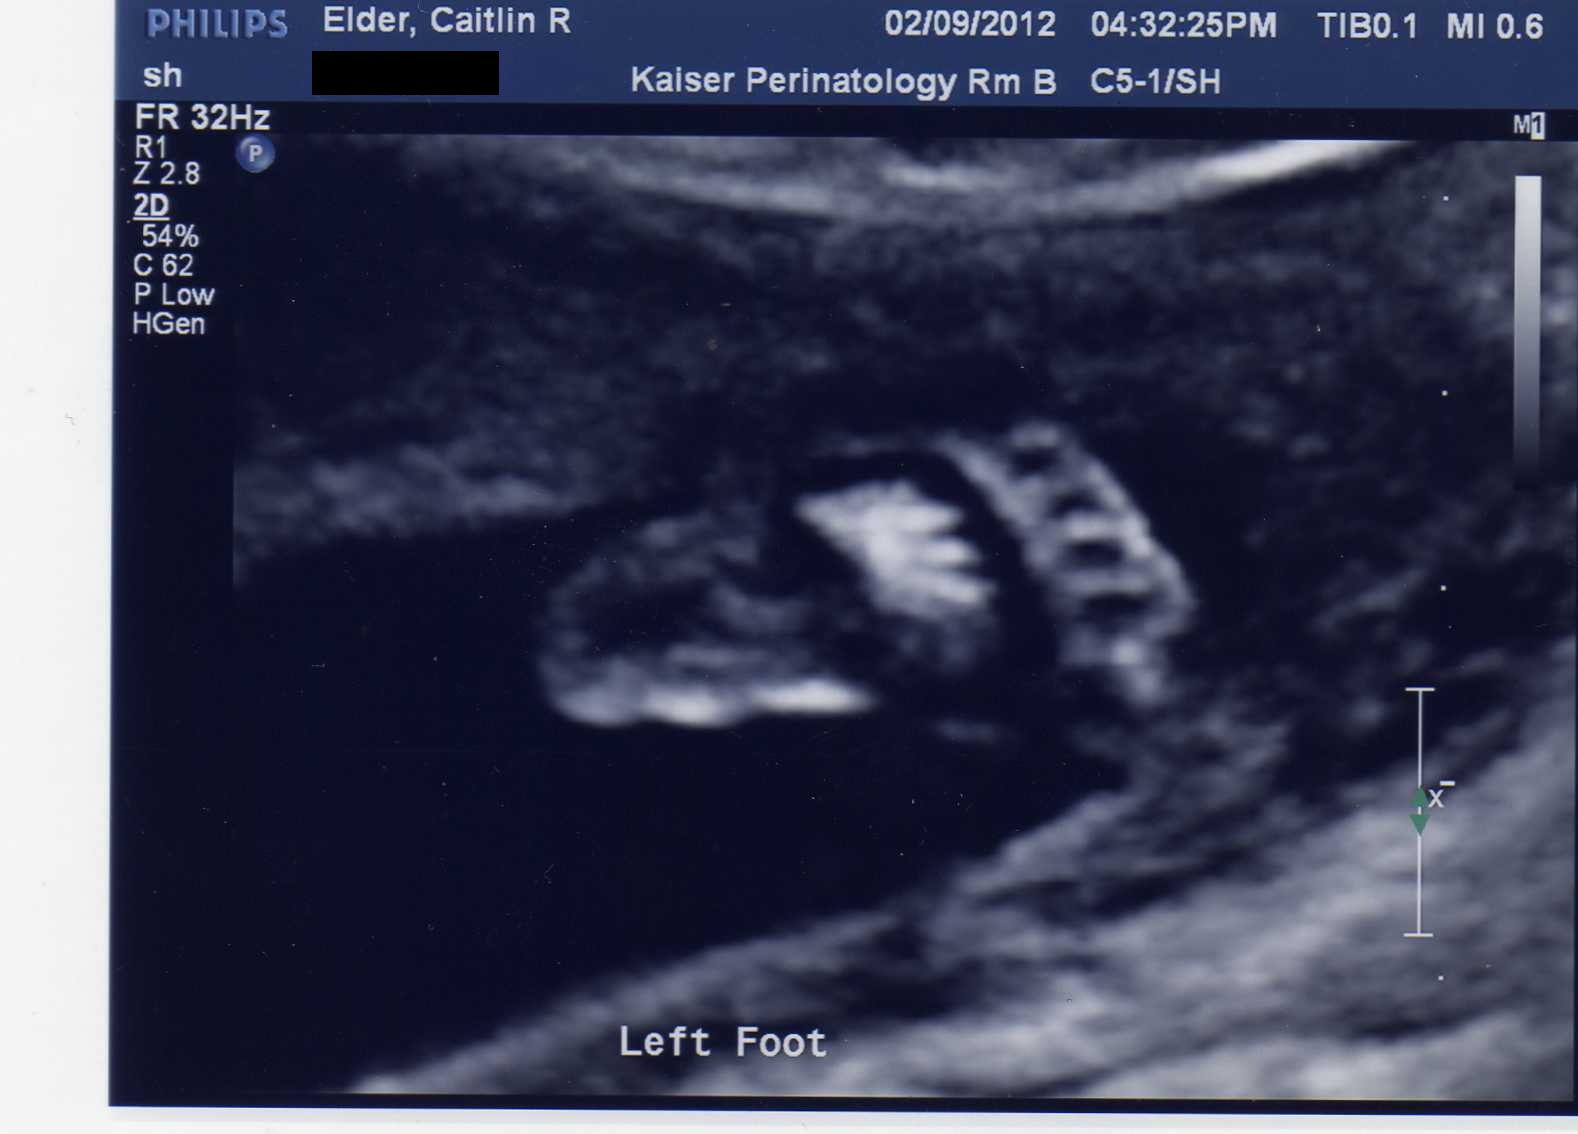

There will be more differences, I’m sure. But for now, I think that’s enough. Here’s one of the most adorable photos we have of #2 so far.